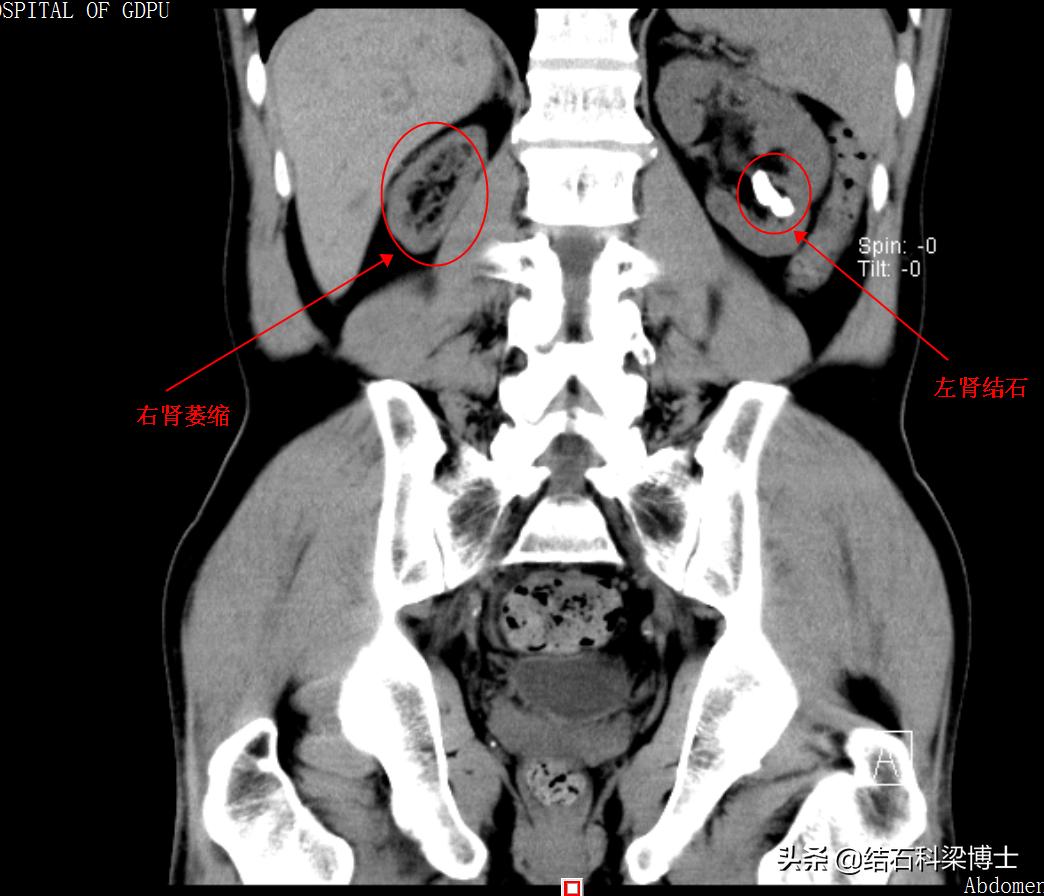

56岁湖南大叔杨某,几年前发现肾结石,当时医生建议手术,而他由于经济原因,自行去小门诊做体外碎石。如今又发现左肾结石,他依然去做体外碎石,结果做了几次后并没有好转,于是到当地县医院就诊。这一检查,才发现患者右肾已经萎缩了,左肾结石伴肾积水,且肾功能不全,县医院做了简单药物治疗并建议患者尽早去省城大医院做手术,这一次,该如何保住他唯一的肾。

患者术前DR可见右肾萎缩、左肾长条形结石一枚

2020年5月13日,患者杨某及家属就诊。由于前期在网上进行了预约,因此没有排队等候,且鉴于其病情特殊,临床中心主任黄苏宁教授自己接诊。了解症状、看过去的检查报告、询问病史,并随后做进一步检查。各项检查结果显示,患者右肾萎缩,左肾有颗结石,伴有肾积水,由于左肾做了体外碎石导致肾功能受损,肌酐值达340umol/L(正常范围应该在130以内)。